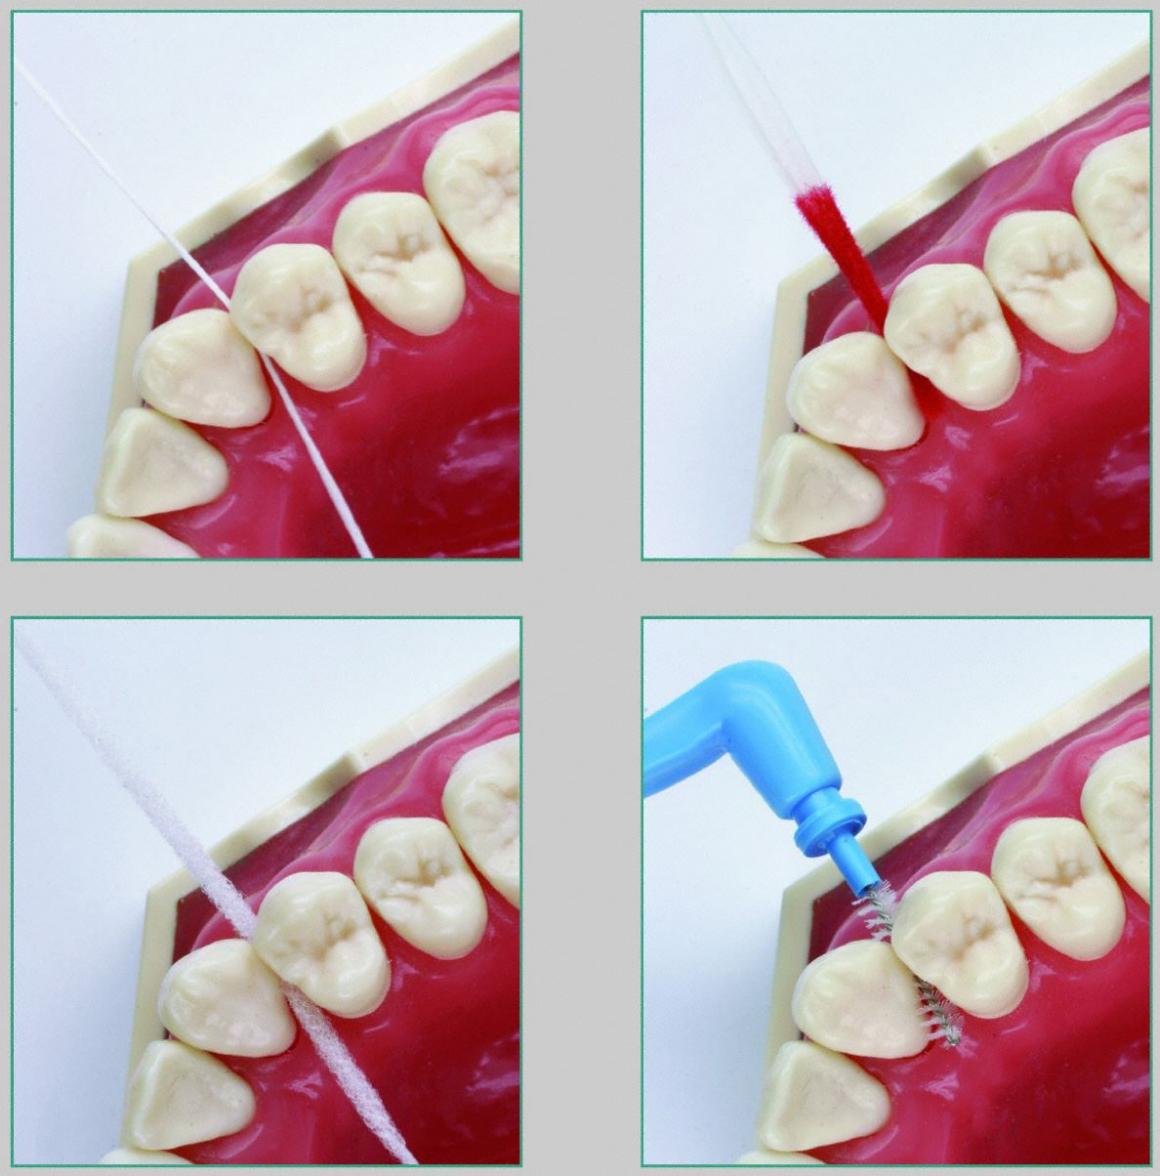

Bei Parodontitis-Patienten ist der Interdentalraum in der Regel erweitert und daher besonders zu beachten und zu behandeln.

Für die möglichst langfristige Erhaltung des Behandlungsergebnisses ist die systematische, regelmäßige und intensive Säuberung des Zwischenraumes eine wichtige Voraussetzung. Dazu braucht der Parodontitis-Patient Hilfsmittel wie Zahnseide, Zahnhölzer, Flauschzahnseide und Interdentalbürstchen.